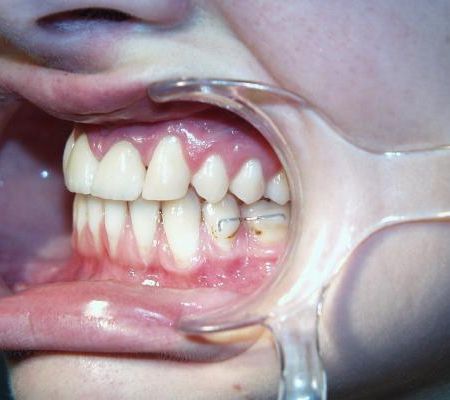

Während der Behandlung

Gleich nach Entfernung der zerstörten mittleren Schneidezähne wurde die feste Zahnspange eingesetzt. Im Bereich der Lücken wurden mit Brackets beklebte Prothesenzähne angebracht. Mit fortschreitender Verkleinerung der Lücke wurde nur noch ein Prothesenzahn belassen (mittleres Bild), der schließlich auch entfernt werden konnte. Die seitlichen Schneidezähne wurden so auf Lücke gestellt, daß sie nach Verbreiterung die Größe von mittleren Schneidezähnen annehmen konnten. Die Eckzähne wurden an Stelle der seitlichen Schneidezähne bewegt (rechtes Bild).